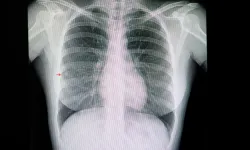

KOAH’ın tanısında solunum fonksiyon testlerinin (nefes testleri) belirleyici olduğunu vurgulayan Anadolu Sağlık Merkezi Hastanesi’nden Göğüs Hastalıkları Uzmanı Doç. Dr. Tayfun Çalışkan, “Bu testler sayesinde hastalığın evresi ve akciğer kapasitesindeki kayıp net biçimde ortaya çıkar. Tedavide sigarayı bırakmaya yönelik medikal destekler, düzenli egzersiz ve solunum rehabilitasyonu büyük önem taşır. Ayrıca grip ve zatürre aşıları, oksijen tedavisi ve ileri evrelerde yapılan bazı özel akciğer girişimleri sayesinde hastaların nefes alma konforu ve günlük yaşamı belirgin biçimde iyileştirilebilir” açıklamasında bulundu.

KOAH’ın gerek toplumda gerekse bazı hekimler arasında yeterince tanınmadığı için çoğu zaman doğru biçimde teşhis edilemediğini ve bu nedenle eksik ya da hatalı tedavi yaklaşımlarına maruz kalabildiğini belirten Doç. Dr. Çalışkan, “Oysa hastalığın erken evrede doğru biçimde tanımlanması, toplum sağlığı açısından son derece önemli. Kronik Obstrüktif Akciğer Hastalığı, genellikle tütün ürünlerinin kullanımı veya zararlı gaz ve partiküllere uzun süre maruz kalma sonucu ortaya çıkar. Ancak doğru tedbirlerle büyük ölçüde önlenebilir ve erken tanı ile kontrol altına alınabilir bir hastalık olduğu unutulmamalı” dedi.